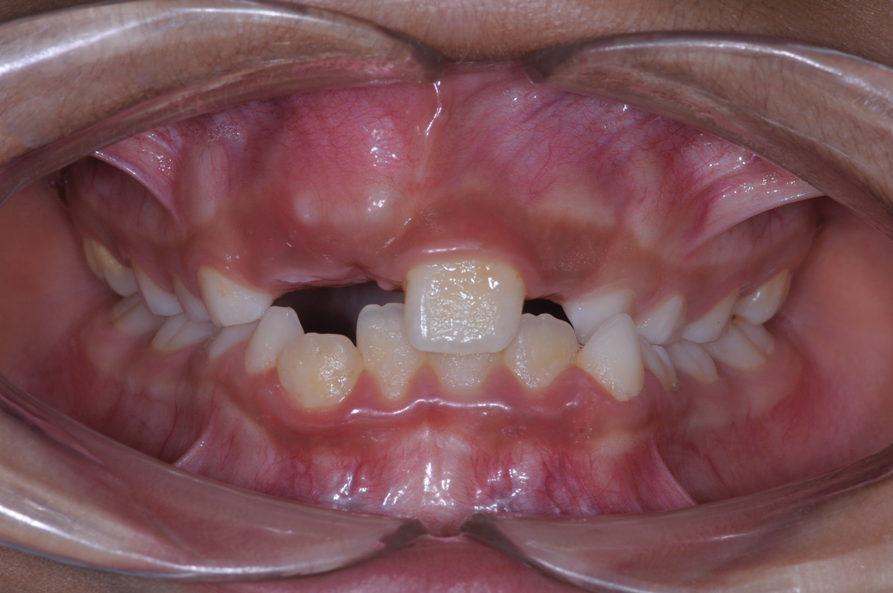

The following case illustrates the complete surgical/orthodontic treatment sequence for an impacted maxillary right central incisor. An 8½-year-old patient presented with a chief complaint of crowded teeth. The maxillary left central incisor was the only erupted incisor at the time of consultation (Figure 2 and Figure 3). Crowding was clinically diagnosed visually by the prominence of the unerupted right central incisor in the vestibule, and this was confirmed with a panoramic radiograph (Figure 4).

Fig 2. Initial situation of case involving an impacted maxillary right central incisor, frontal view (Fig 2) and occlusal view (Fig 3).

Figure 2

Fig 3. Initial situation of case involving an impacted maxillary right central incisor, frontal view (Fig 2) and occlusal view (Fig 3).

Figure 3